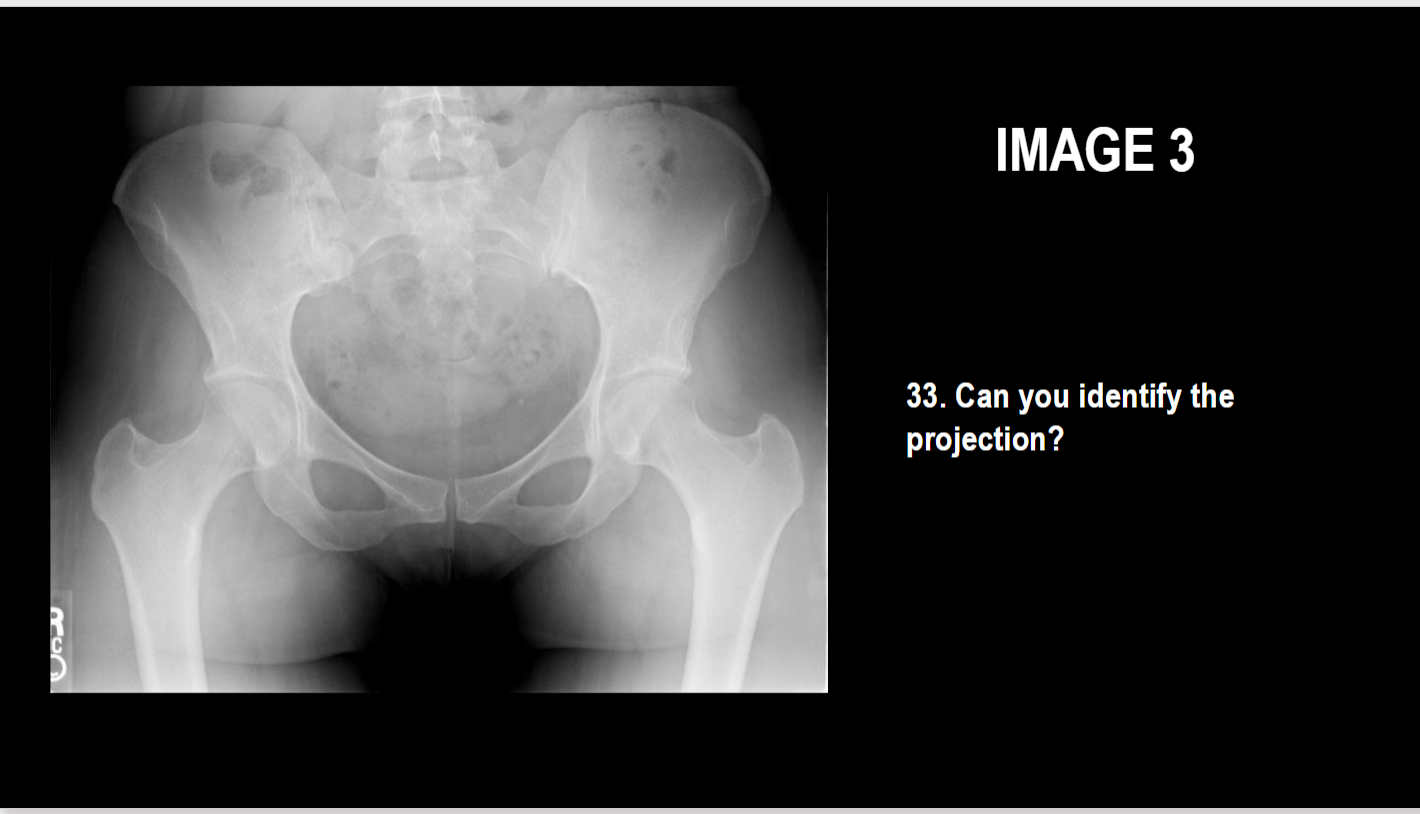

What projection is this

AP Pelvis

Projection?